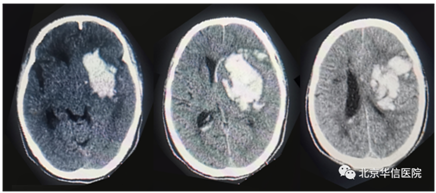

脑出血患者术前头颅CT

患者入院时处于昏迷状态,危在旦夕,情况紧急。经快速周密的术前准备和评估,在麻醉科、手术室的密切配合下,由应建有和焦庆贵主治医师为患者精准实施神经内镜下基底节区脑内血肿清除手术。术中仅在患者头部做一约4cm长的小切口,操作范围为稍大于一元硬币的微骨孔,术中应用气动支持臂辅助,在神经内镜“慧眼”的指引下,电凝出血点,紧张有序地探查血肿并予以清除,术后2小时复查头部CT显示血肿清除干净,手术起到立竿见影的效果。